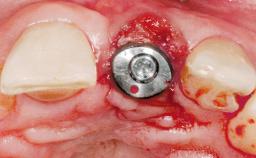

Late Placement of an Implant in a Maxillary Left Central Incisor Site

A 36-year-old female patient was referred for the replacement of the upper left central incisor (tooth 21), which had fractured. Although the tooth had been asymptomatic for many years, the crown began to loosen, at which time she presented to her dentist for an assessment. Teeth 21 and 22 had both been endodontically treated many years previously. She was a healthy individual and a non-smoker.

# of Implants 1

Type of Implants Two-Piece

Bone Volume Deficient horizontally, requiring prior grafting